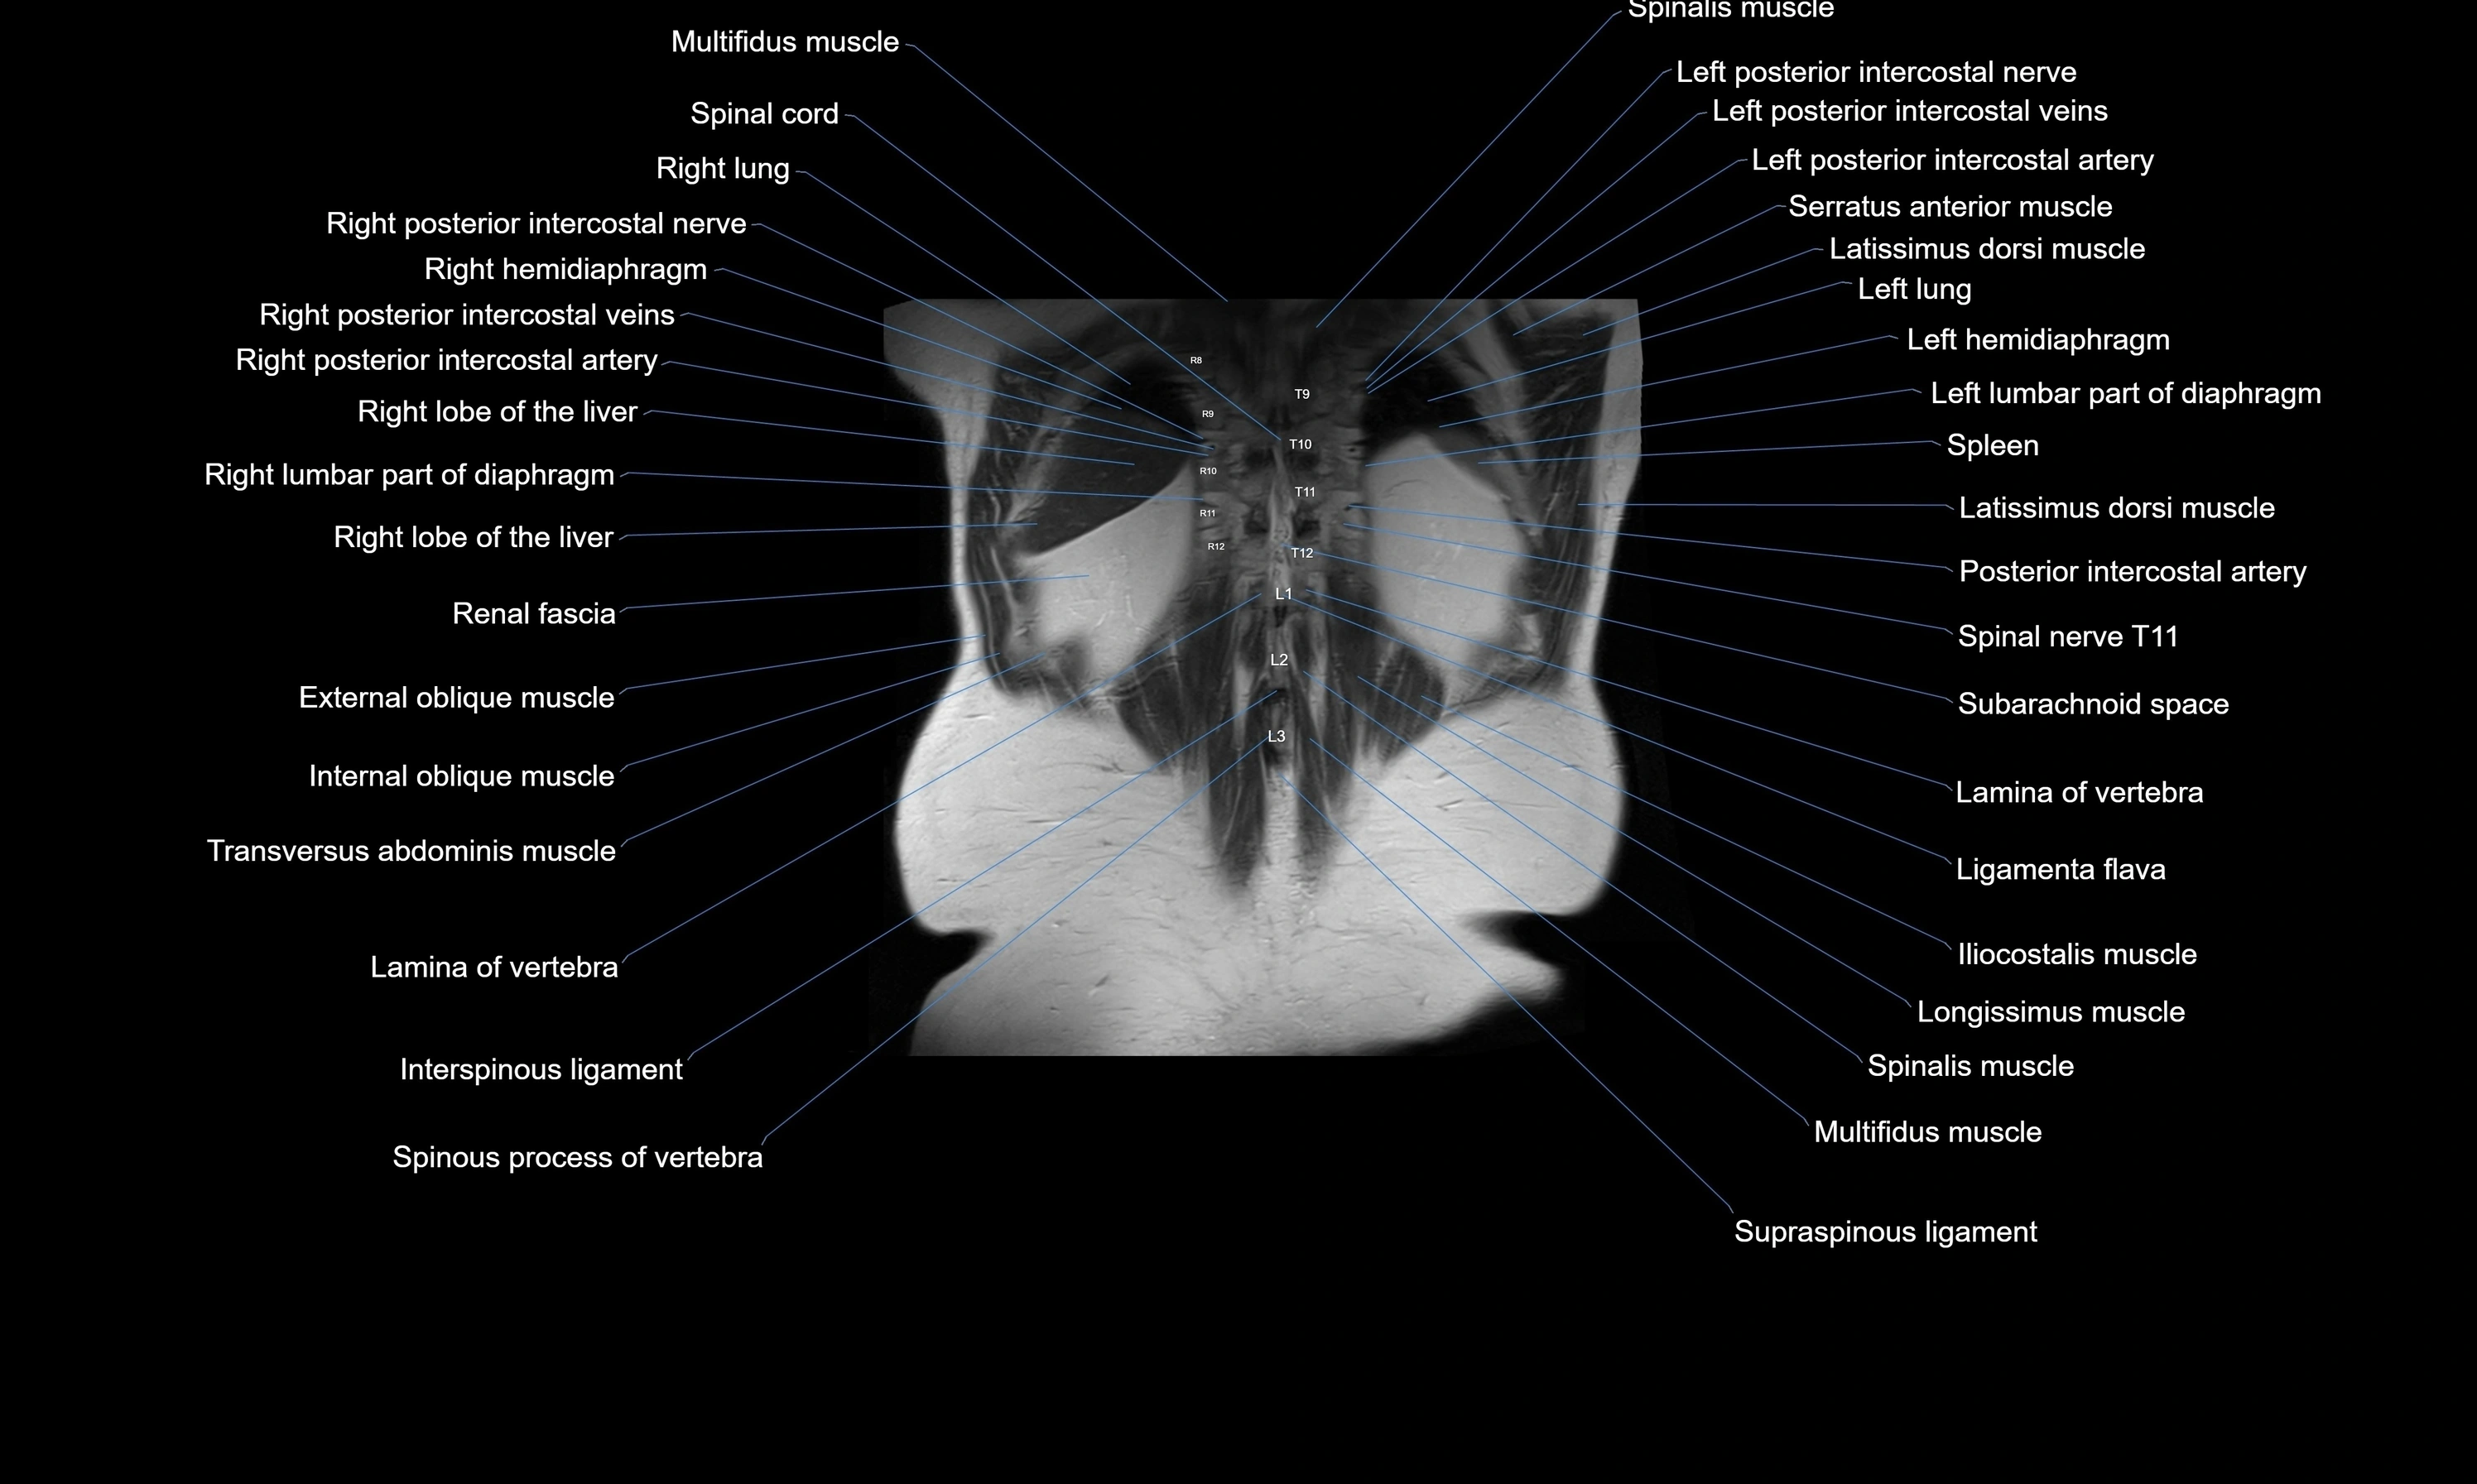

MRI images